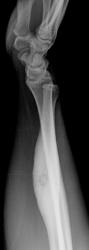

Татьяна Валентиновна представила интересный, классический случай "Остеоид-остеома".

Татьяна Валентиновна обращает внимание, что в данном случае имеют место, все классические признаки данного патологического процесса:

- выраженный гиперостоз;

- очаг разряжения - "гнездо";

- с более плотным включением - "яйцо в гнезде".